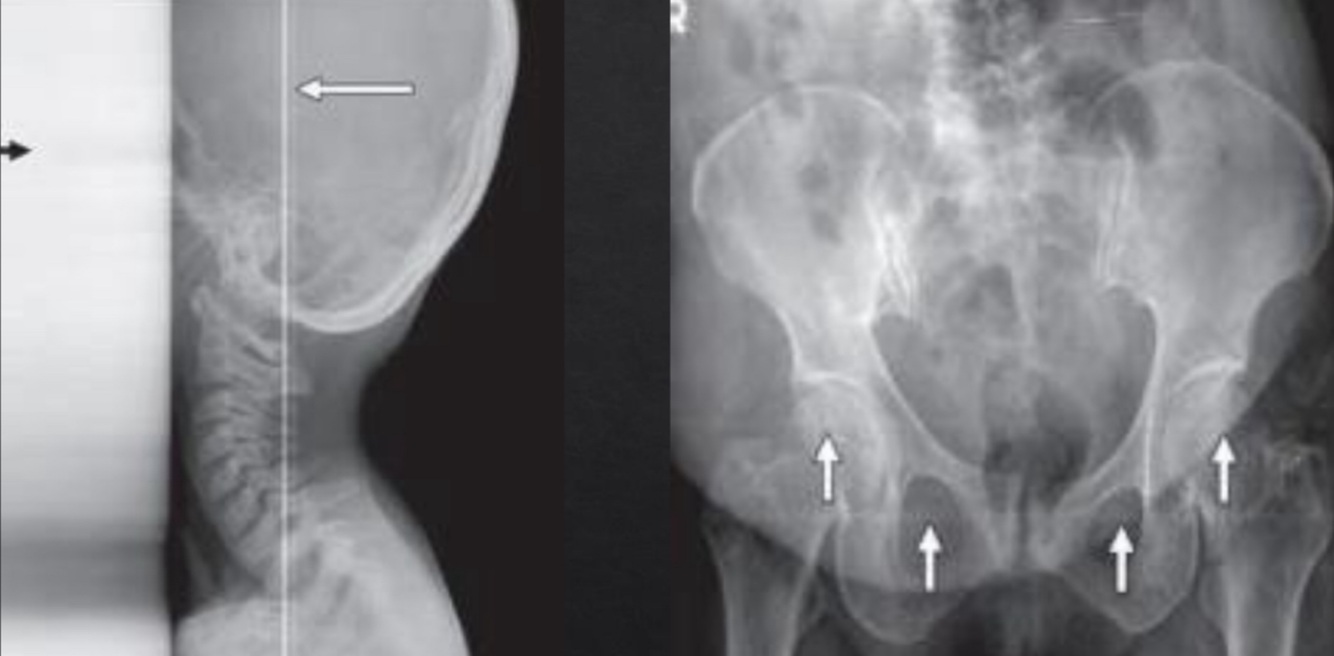

Example 2: On a Agfa system an exposure of 85 kVp at 40mAs of a CTL hip resulted in a lgM of 2.0. What change in mAs is needed to bring the lgM to the median of 2.6?

Double the mAs TWICE (40x2= 80, 80x2= 160) to get the exposure indicator (IgM) to. 2.6 -Explanation: The lgM is the logarithm of the median exposure. The median exposure for this system is 2.6. The exposure indicator is directly related, therefore a lgM of 2.0 is underexposed. For each doubling of the mAs a 0.3 increase of the lgM would result. If the radiographer increase the mAs 4X to 160 mAs, this change would increase the lgM by 0.6 and bring it to about 2.6, which is the median suggested by the manufacturer.